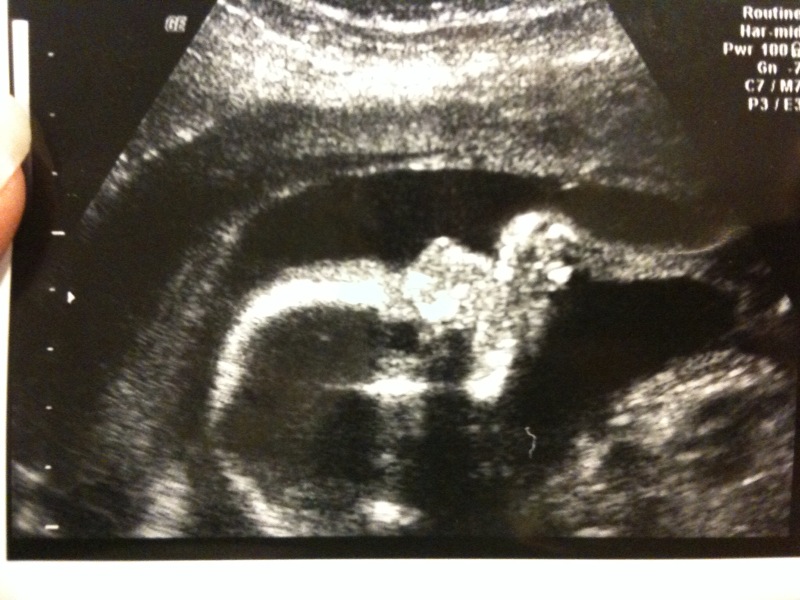

Bekräftat till 100% att the girl parts är på plats

Suger på fingrarna 🙂

Profilbild med en liten hand 🙂